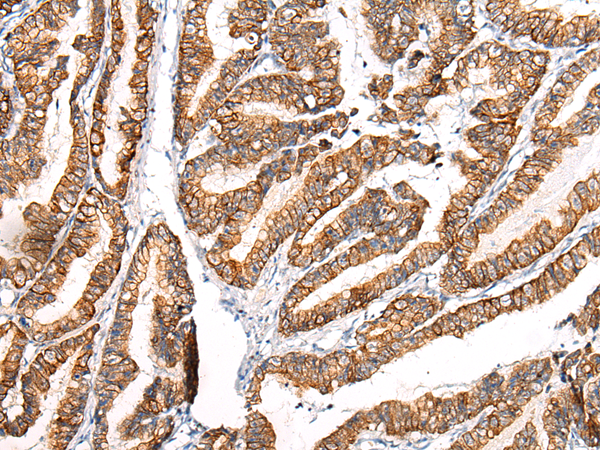

分类: 科研抗体货号: P12486别名: CDX3; CDX-3; CDX2/AS应用: WB,IHC反应种属: Human, Mouse